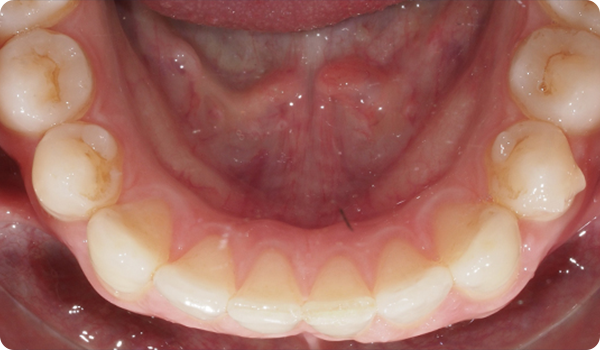

De praktijk stuurt drie foto's en het STL-bestand van een scan via Corus Link om de casus te beoordelen.